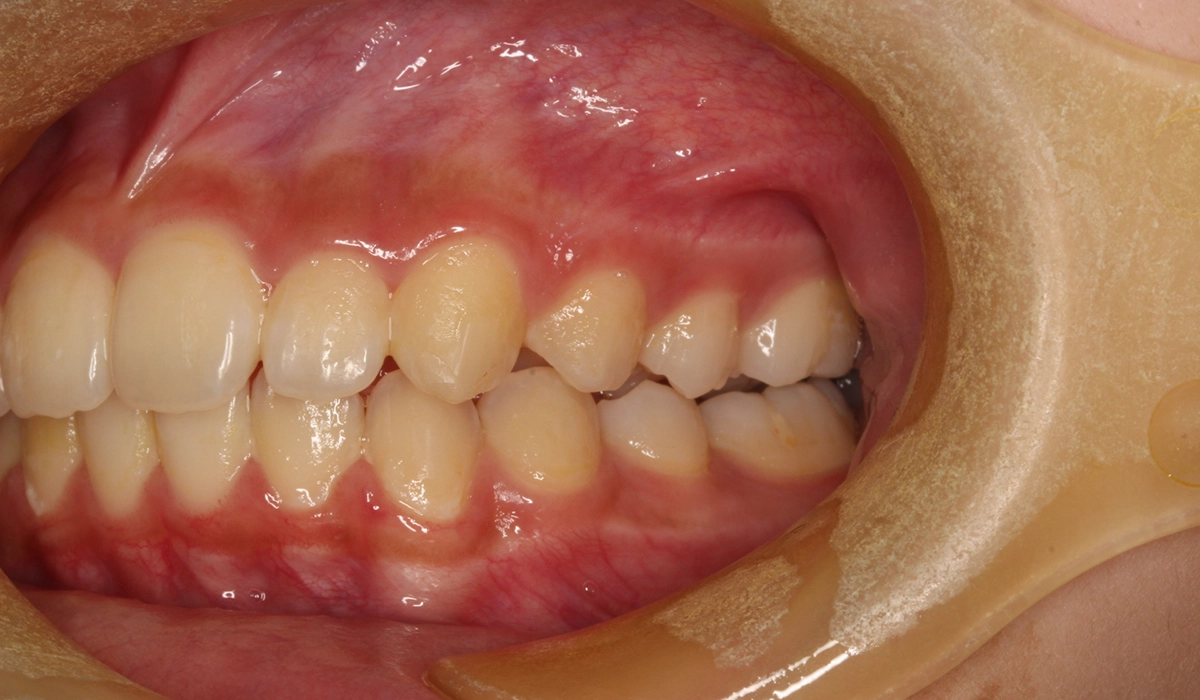

術前:左側

術後:左側